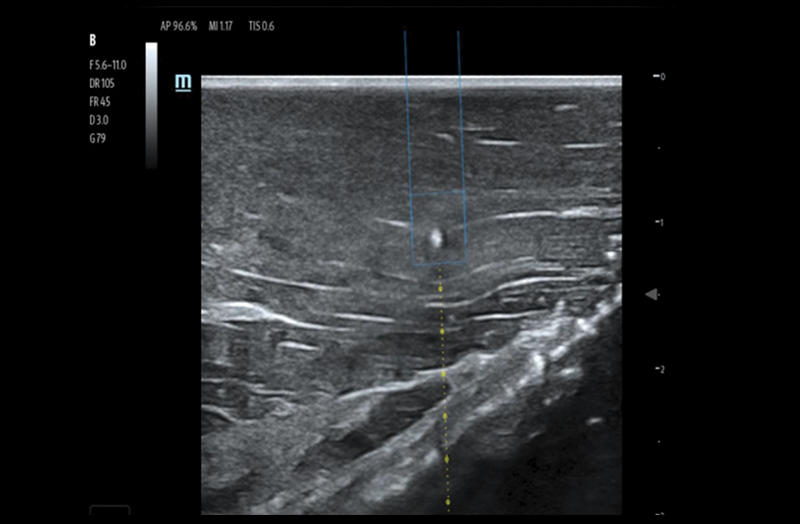

Needle Guidance

Clinical Images